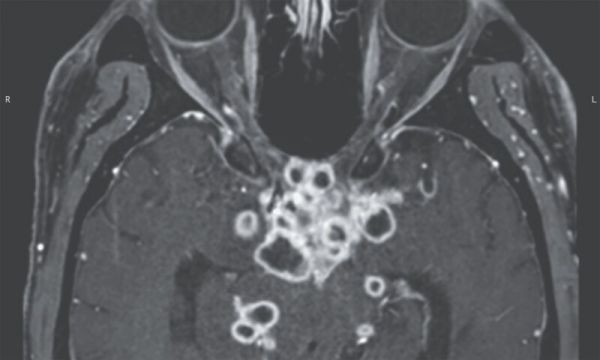

头部 MRI:视交叉、视神经束附近有多个环状增强病变。

青年男性,急性起病,表现为头痛、视物模糊,查体双眼视力下降,头颅核磁共振检查示颅底强化,环形强化,壁薄。

肿瘤是不太可能的,病变比较分散,如果是肿瘤血源播散,一般都会在靠近脑膜的皮层或皮层下,同时水肿明显。

而该例病变完全在脑膜,脑膜肿瘤,例如脑膜癌,都形成不了环形的病变,中枢原发更不可能。

只会是感染、结核瘤、隐球菌结节肉芽肿都可能,更倾向结核。

患者脑脊液核酸扩增检测发现结核分枝杆菌,同时有结肠结核,确诊为「结核性视交叉蛛网膜炎」,属于结核性脑膜炎的并发症,因为渗出物导致视神经和视交叉蛛网膜发炎,从而出现视力丧失。 临床表现,影像表现都是挺典型的。